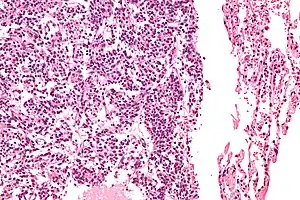

O diagnóstico definitivo é alcançado por um exame microscópico, após excisão. Os tumores carcinoides típicos apresentam células com cromatina pontilhada e uma quantidade moderada de citoplasma. Eles realizam menos mitoses e têm uma baixa necrose. Por definição, eles sã0 maiores do que 4 mm em sua maior dimensão.